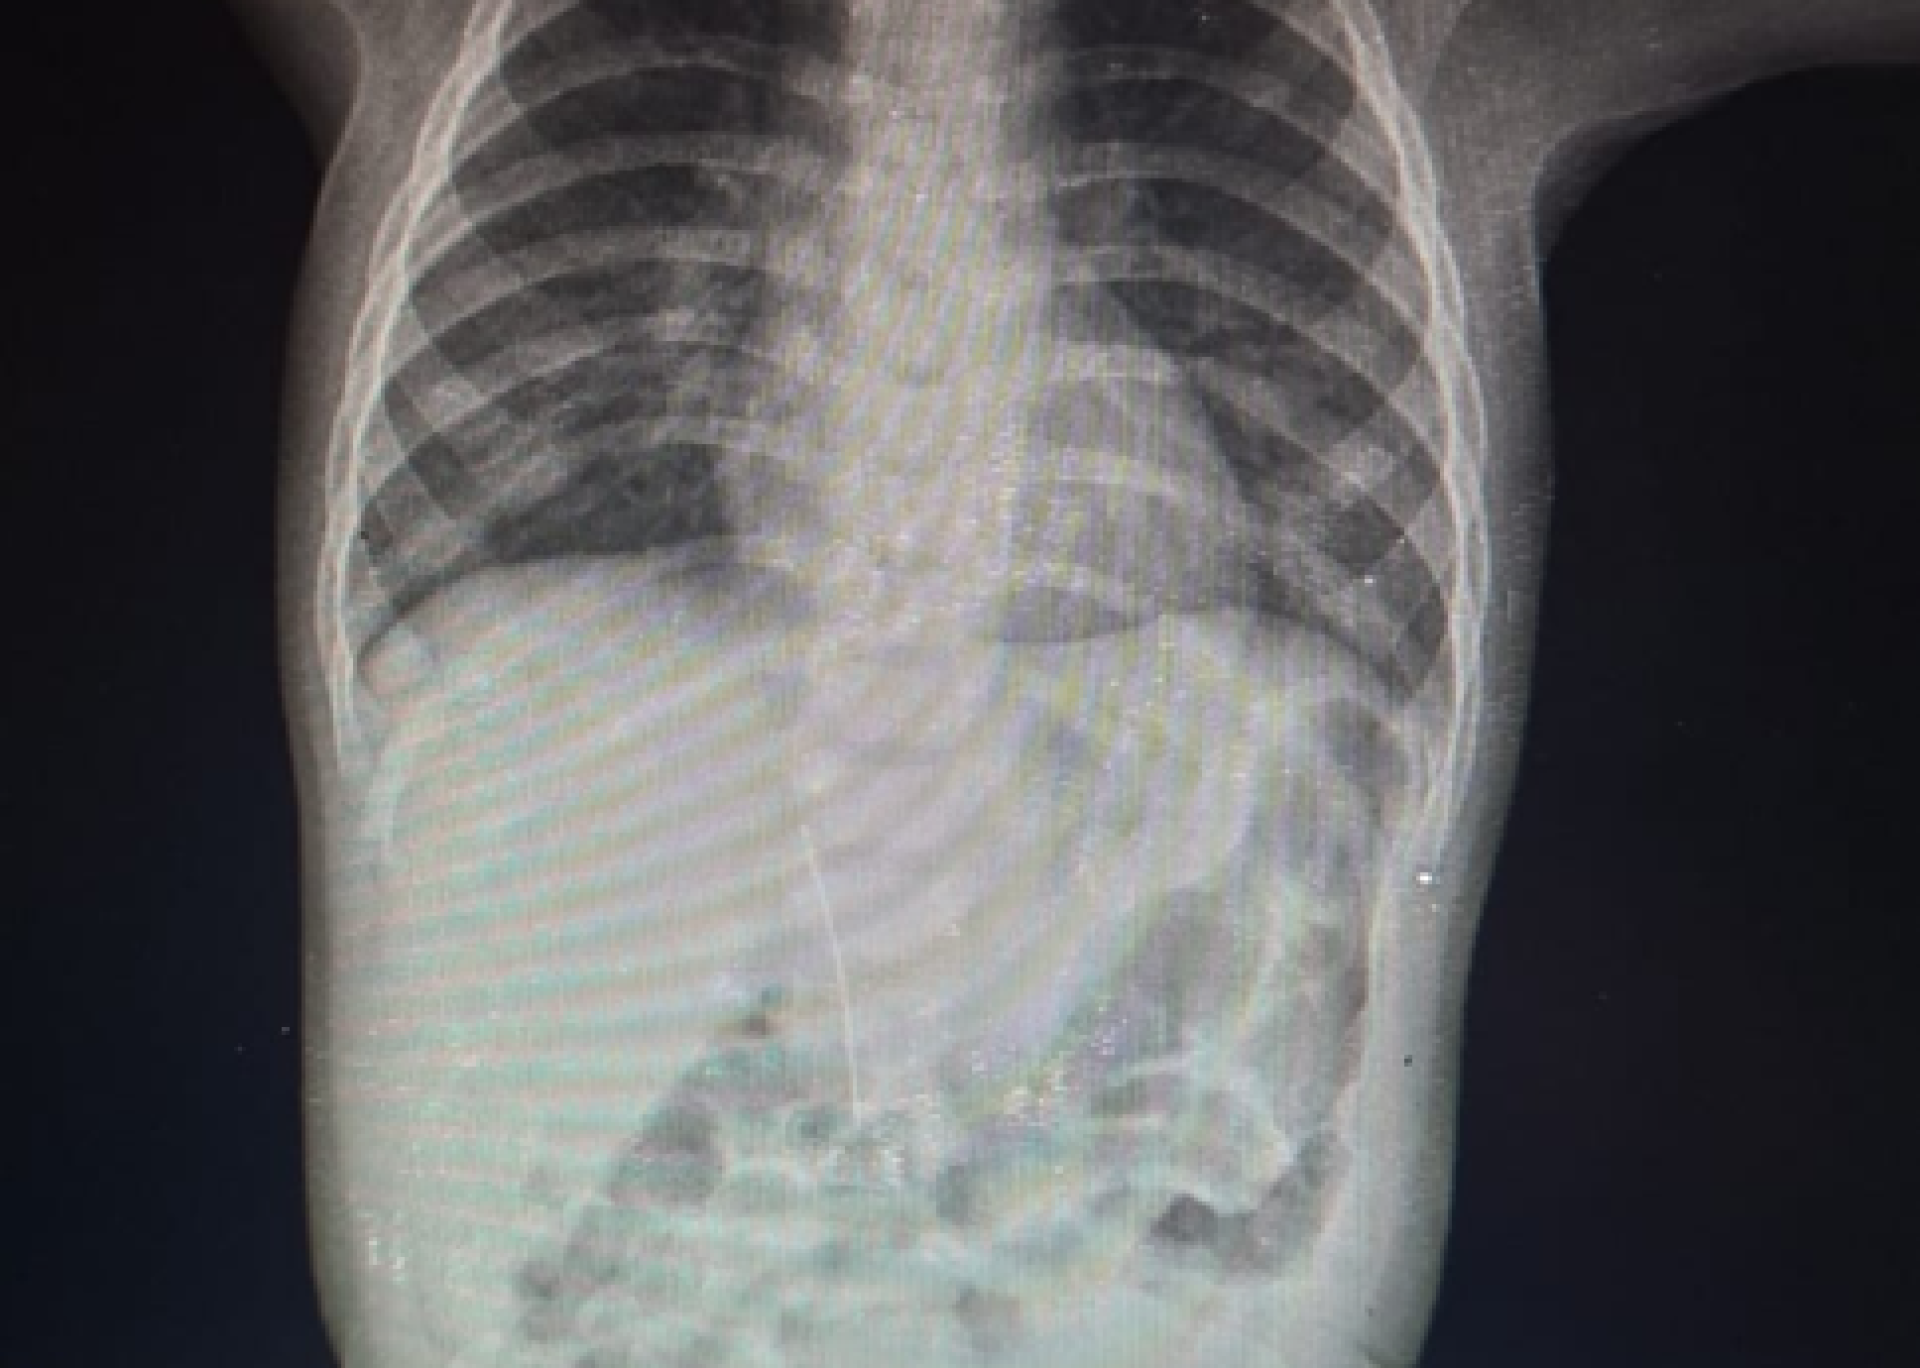

В инфекционное отделение Туркестанской городской центральной больницы был доставлен 8-месячный ребёнок с подозрением на краснуху. Врачи провели рентгенологическое исследование и обнаружили в брюшной полости малыша иглу, передаёт Tengrinews.kz.

Как выяснилось, беспокойство ребёнка и повышение температуры тела были вызваны не инфекцией, а именно воздействием инородного предмета.

По словам врачей, игла попала в организм не через пищеварительный тракт. Она проникла со стороны печени. Мать ребёнка отметила, что малыш не мог самостоятельно проглотить её.

Фото предоставлено управлением здравоохранения региона